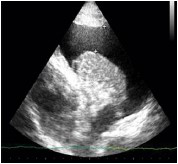

Paciente de 70 anos do sexo masculino dá entrada no Pronto-Socorro após iniciar quadro de dispneia em churrasco, há cerca de 1 hora.

Relata ser hipertenso e ter insuficiência cardíaca. Ao exame clínico, dispneico, FR 30, SatO2 77% em ar ambiente, FC 110 e PA 190x120, com ausculta pulmonar com estertores finos até ápices.

Assinale a opção que apresenta a imagem de ultrassonografia pulmonar compatível com a descrição do quadro acima.